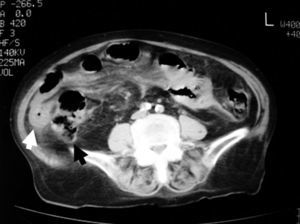

Las pruebas complementarias realizadas al ingreso son hemograma (hemoglobina de 11,1g/dl; hematocrito de 34%, y conteo de leucocitos de 8.63/l, con fórmula normal) y bioquímica (glucemia de 110mg/dl; creatinina de 1,4mg/dl; amilasa de 22U/l; sodio de 139mEq/l; potasio de 3,9mEq/l, proteína C reactiva de 125U). En la radiografía de tórax se observa derrame pleural derecho, sin neumoperitoneo. En la radiografía de abdomen se observa distensión moderada de asas de intestino delgado y aire visible en el colon, que es de diámetro normal. En la TC abdominal se visualiza engrosamiento segmentario de un asa del intestino delgado con discreta dilatación del asa proximal a ésta, que en el estudio sin contraste se encuentra localizada en la gotiera derecha, con desplazamiento anterior y medial del ciego, con los vasos mesentéricos elongados y dirigidos hacia esa asa (fig. 1). Tras la administración de contraste oral, esa asa se desplaza hacia el mesogastrio, con cambio de orientación de los vasos mesentéricos; el engrosamiento segmentario y concéntrico de la pared persiste (fig. 2). Hay una pequeña cantidad de líquido libre en ambas gotieras y pelvis.

Con el diagnóstico de hernia pericecal reducida, la paciente permanece en observación; se le retira la anticoagulación oral, y presenta una buena evolución clínica y radiológica.

Las hernias pericecales son una rara causa de obstrucción intestinal pero que han de tenerse en cuenta, sobre todo si no hay antecedentes quirúrgicos ni hernias inguinocrurales. Su diagnóstico es posible mediante TC abdominal con contraste. En cuadros de pocas horas de evolución es posible su reducción espontánea con resolución del proceso, antes de evolucionar hacia la perforación intestinal y, en ocasiones (como en el caso presentado), la administración de contraste oral puede producir la reducción mecánica de la hernia interna. En cualquier caso, tras la resolución no quirúrgica del cuadro, es preciso la reducción de la hernia y la corrección del defecto por vía laparoscópica o mediante laparotomía.